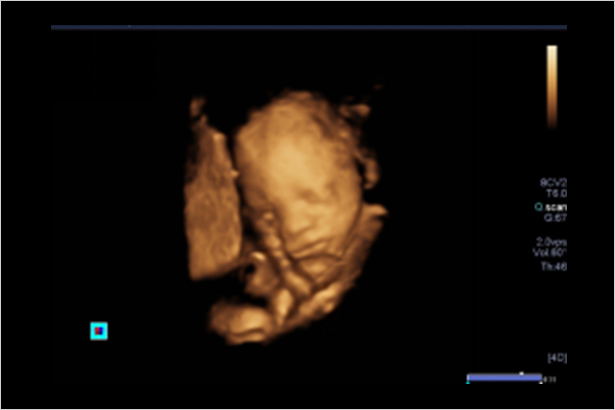

一整套完備的解決方案,具有全面的成像模式,包括表面成像,斷層切面成像和多平面重建成像等